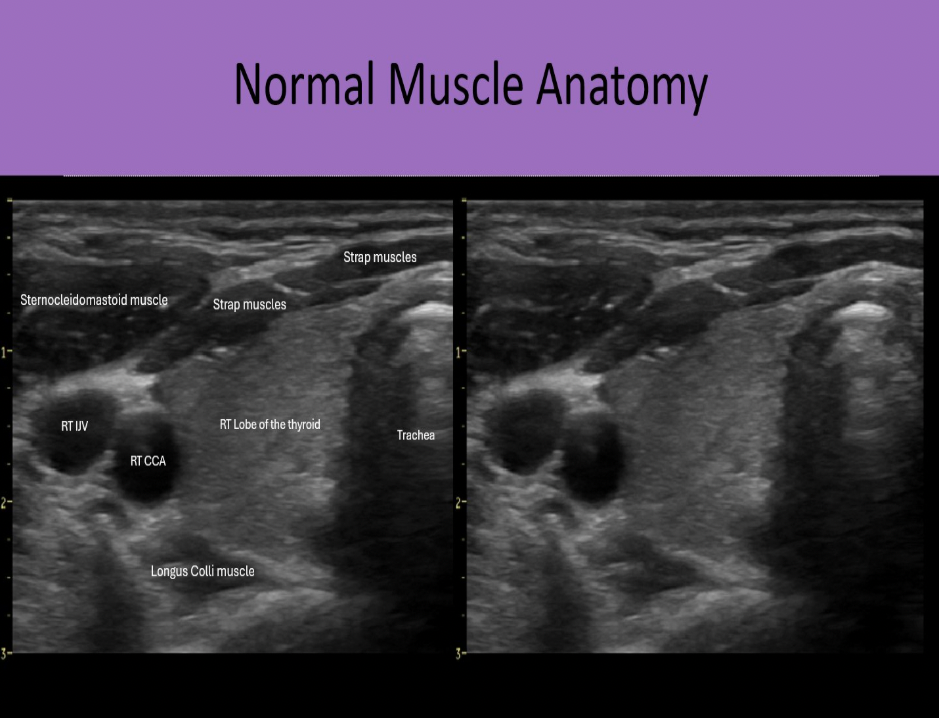

Which muscle group is located posterior to the thyroid gland?

C. longus colli muscle

Strap muscles are anteromedial to the gland. Sternocleidomastoid muscles are anterolateral to the gland. Longus Colli muscles are posterior to the thyroid lobes.

Find the sternocleidomastoid muscle

The sternocleidomastoid muscles are anterolateral to the thyroid gland

Which muscle group is located anterolateral to the lobes of the thyroid gland?

C. sternocleidomastoid

Which muscle group is located anteromedial to the lobes of the thyroid gland?

C. strap muscles

Which of the following structures is labeled #6?

A. Longus Colli muscle

Right lobe of the thyroid

Right carotid artery

Right internal jugular vein

Sternocleidomastoid muscle

Strap muscles

Longus colli muscle